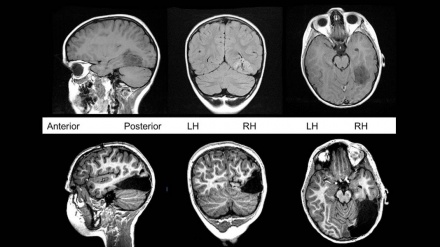

• Koronavirusun insan beynindəki fəsadları aşkarlanıb

Koronavirusun insan beynindəki fəsadları aşkarlanıb

İyul 09, 2020 17:26

London Universiteti Kollecinin (UCL) tədqiqatçıları COVID-19 üzündən beyin xəstəliklərinin artacağı qənaətinə gəliblər.